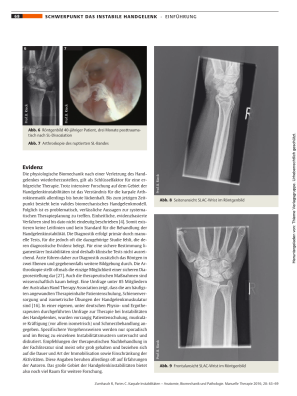

Besonders häufig ist die skapholunäre Dissoziation (DISI), bei der es zu einer Fehlstellung des Lunatums kommt, die unbehandelt in einen Scapholunate Advanced Collapse (SLAC-Wrist) übergehen kann.

Diagnostisch ist die Arthroskopie derzeit das sicherste Verfahren.